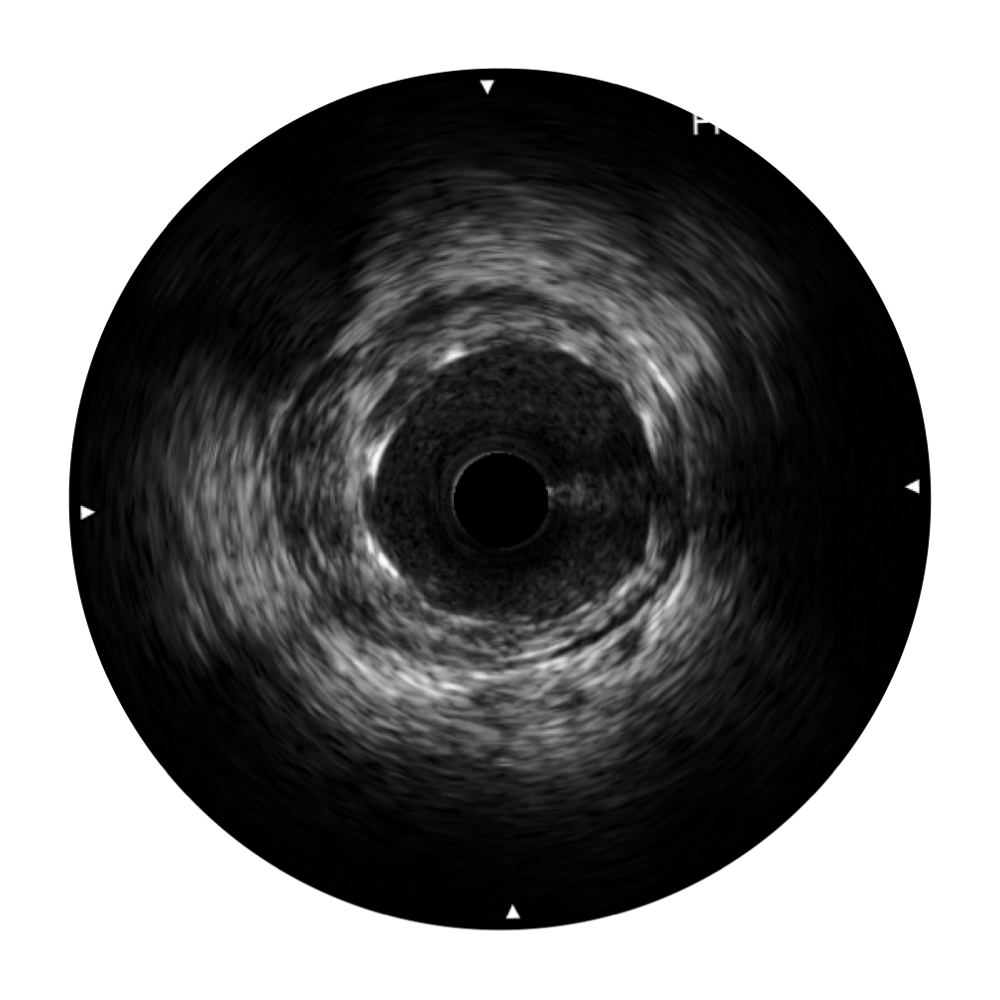

血管内超声(IVUS) 通过对病变程度、性质和累及范围的精确判断,可帮助选择治疗策略和方法,指导介入治疗过程,能够降低主要不良心血管事件,改善预后,在复杂病变介入治疗中用于指导支架置入的优势更为明显。血管内超声(IVUS)已成为精准心血管介入治疗的“金标准”。

玖鼎集团始终关注未满足的临床需求:超宽频成像技术同时提供高清分辨力和充足穿透深度,适应不同血管结构的治疗引导;智慧赋能,简化操作,降低临床应用难度和缩短学习曲线。

玖鼎集团超宽频成像技术覆盖20-80MHz1或20-90MHz2频率范围, 提供优异的分辨力同时也保证充足的穿透深度

对比传统IVUS导管成像,玖鼎集团宽频IVUS图像的近场支架梁显影更细腻,远场中膜外血管仍清晰可辨,兼顾远中近,兼顾分辨力与穿透深度